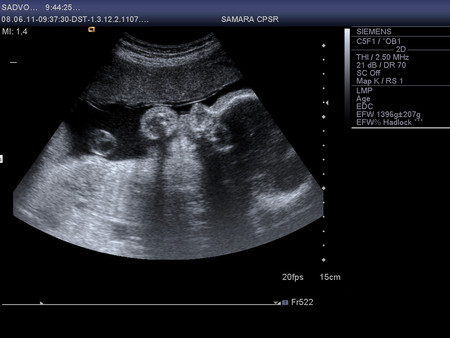

. Он все понимает. Вчера заявил, что обязательно будет присутствовать на родах как и в прошлый раз, т.к. по-другому просто не может и ему будет легче со мной, чем где-то тупо ждать. Мне безусловно приятно. Его присутствие, поддержка, помощь для меня не оценимы. Такая непередаваемая между нами близость была в тот момент и сейчас, когда вспоминаем день рождения нашего ребенка. Ивану тоже достается от меня по полной программе, мне его даже жалко, но я ничего не могу с собой поделать. Порой у меня ощущение,что он просто издевается надо мной. Стал капризным, требовательным, нервным, истерит по любому поводу,если не удовлетворить его просьбу. Толи из-за зубов,которые продолжают резаться,толи из-за огромного прорыва в речи. Стал говорить много слов, повторяет почти все,что произносят взрослые. От мультиков вообще не оторвать. Любимые про котенка "Гав", Карлсона и паровозик из Ромашково. Готов смотреть целыми днями из-за чего у нас с ним бесконечная борьба происходит. В общем последняя неделя в эмоциональном плане была не из легких. На приемы в ЖК езжу теперь каждую неделю, анализы и КТГ хорошие, гемоглобин даже повысился каким-то чудесным образом до 103. Вес 56 кг. Сходила на УЗИ. Лежит головой вниз, обвития нет, кровотоки хорошие, все органы в порядке, вес примерно 1720. Врач сказала,что ребенок небольшой, к родам будет примерно 3100 (Ваня родился 3435). Плацента поднялась до 6 см, как раз то, что нужно. Посмотрела в 4D кажется совсем не похож на Ваню, а Тимка говорит, что копия (наверное очень хочет, чтоб и второй был похож только на него

). А еще он волосатый (первый раз на УЗИ видела волосы), прям длинные волосы торчат на голове.